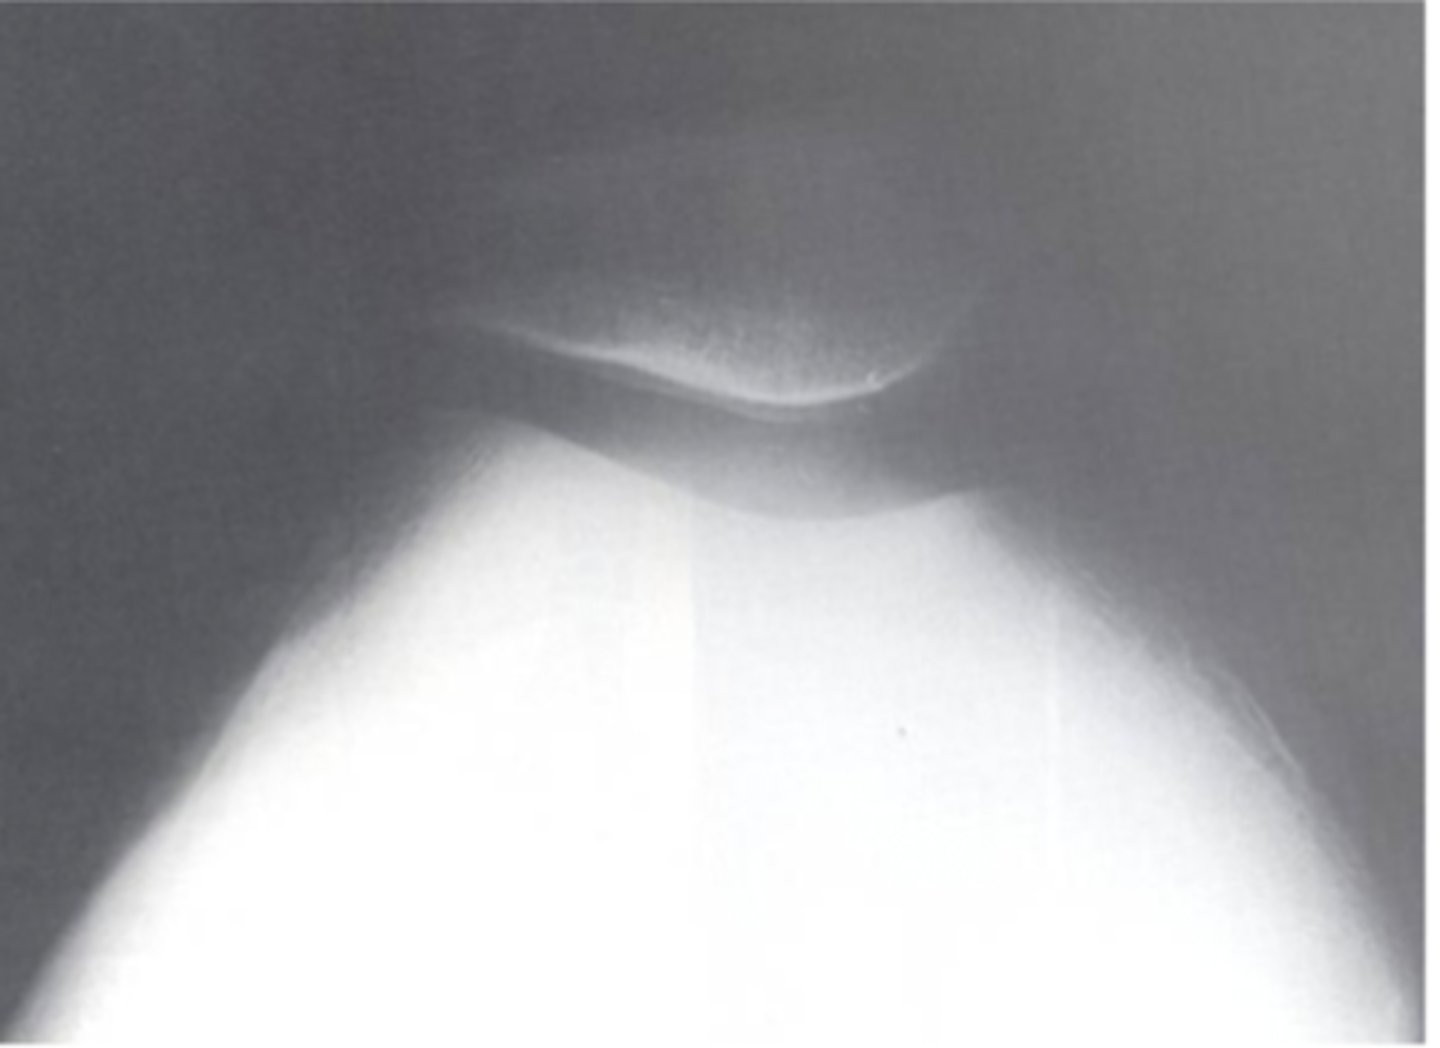

Sunrise or skyline view of Patellofemoral joint

What view does this show?